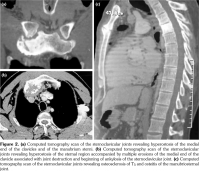

Laboratory examination revealed a slightly elevated C-reactive protein level (16 mg/L) and erythrocyte sedimentation rate (40 mm). Serum levels of calcium, albumin and phosphorus were within the normal range. Blood cell counts, liver tests, and renal function were unremarkable. Blood cultures, urinanalysis, tumor markers, and serodiagnosis for brucella were negative. Tuberculosis skin test was negative. Spine magnetic resonance imaging showed low T1, high T2 signal and contrast enhancement in the T4/T5 and L3 vertebral body and in the T4/T5 disk (Figure 1). Sacroiliac joints were normal. Computed tomography-guided biopsy of the T4/T5 disc demonstrated nonspecific inflammation and culture of this specimen was negative. Computed tomography scan of the sternoclavicular joints revealed hyperostosis and erosions involving the sternum as well as medial end of clavicle (Figure 2). Clavicular biopsy showed irregular sclerotic trabeculae. Human leukocyte antigen B27 typing was positive.

Radiological signs of SAPHO may sometimes be difficult to differentiate from infectious spondylodiscitis and even tumors, leading to a diagnostic delay. Indeed, the intervertebral disc may be narrowed, and, in 10% of cases, magnetic resonance imaging shows high signal intensity on T2-weighted images and gadolinium enhancement, simulating infectious spondylodiscitis.(3-7)